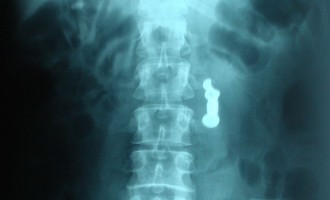

Πήγε στην Κύπρο με κοκαΐνη στο… στομάχι

Το Επαρχιακό Δικαστήριο Λάρνακας διέταξε την 8ήμερη κράτηση του 42χρονου Ολλανδού, ο οποίος συνελήφθη χθες βράδυ κατά την άφιξή του…